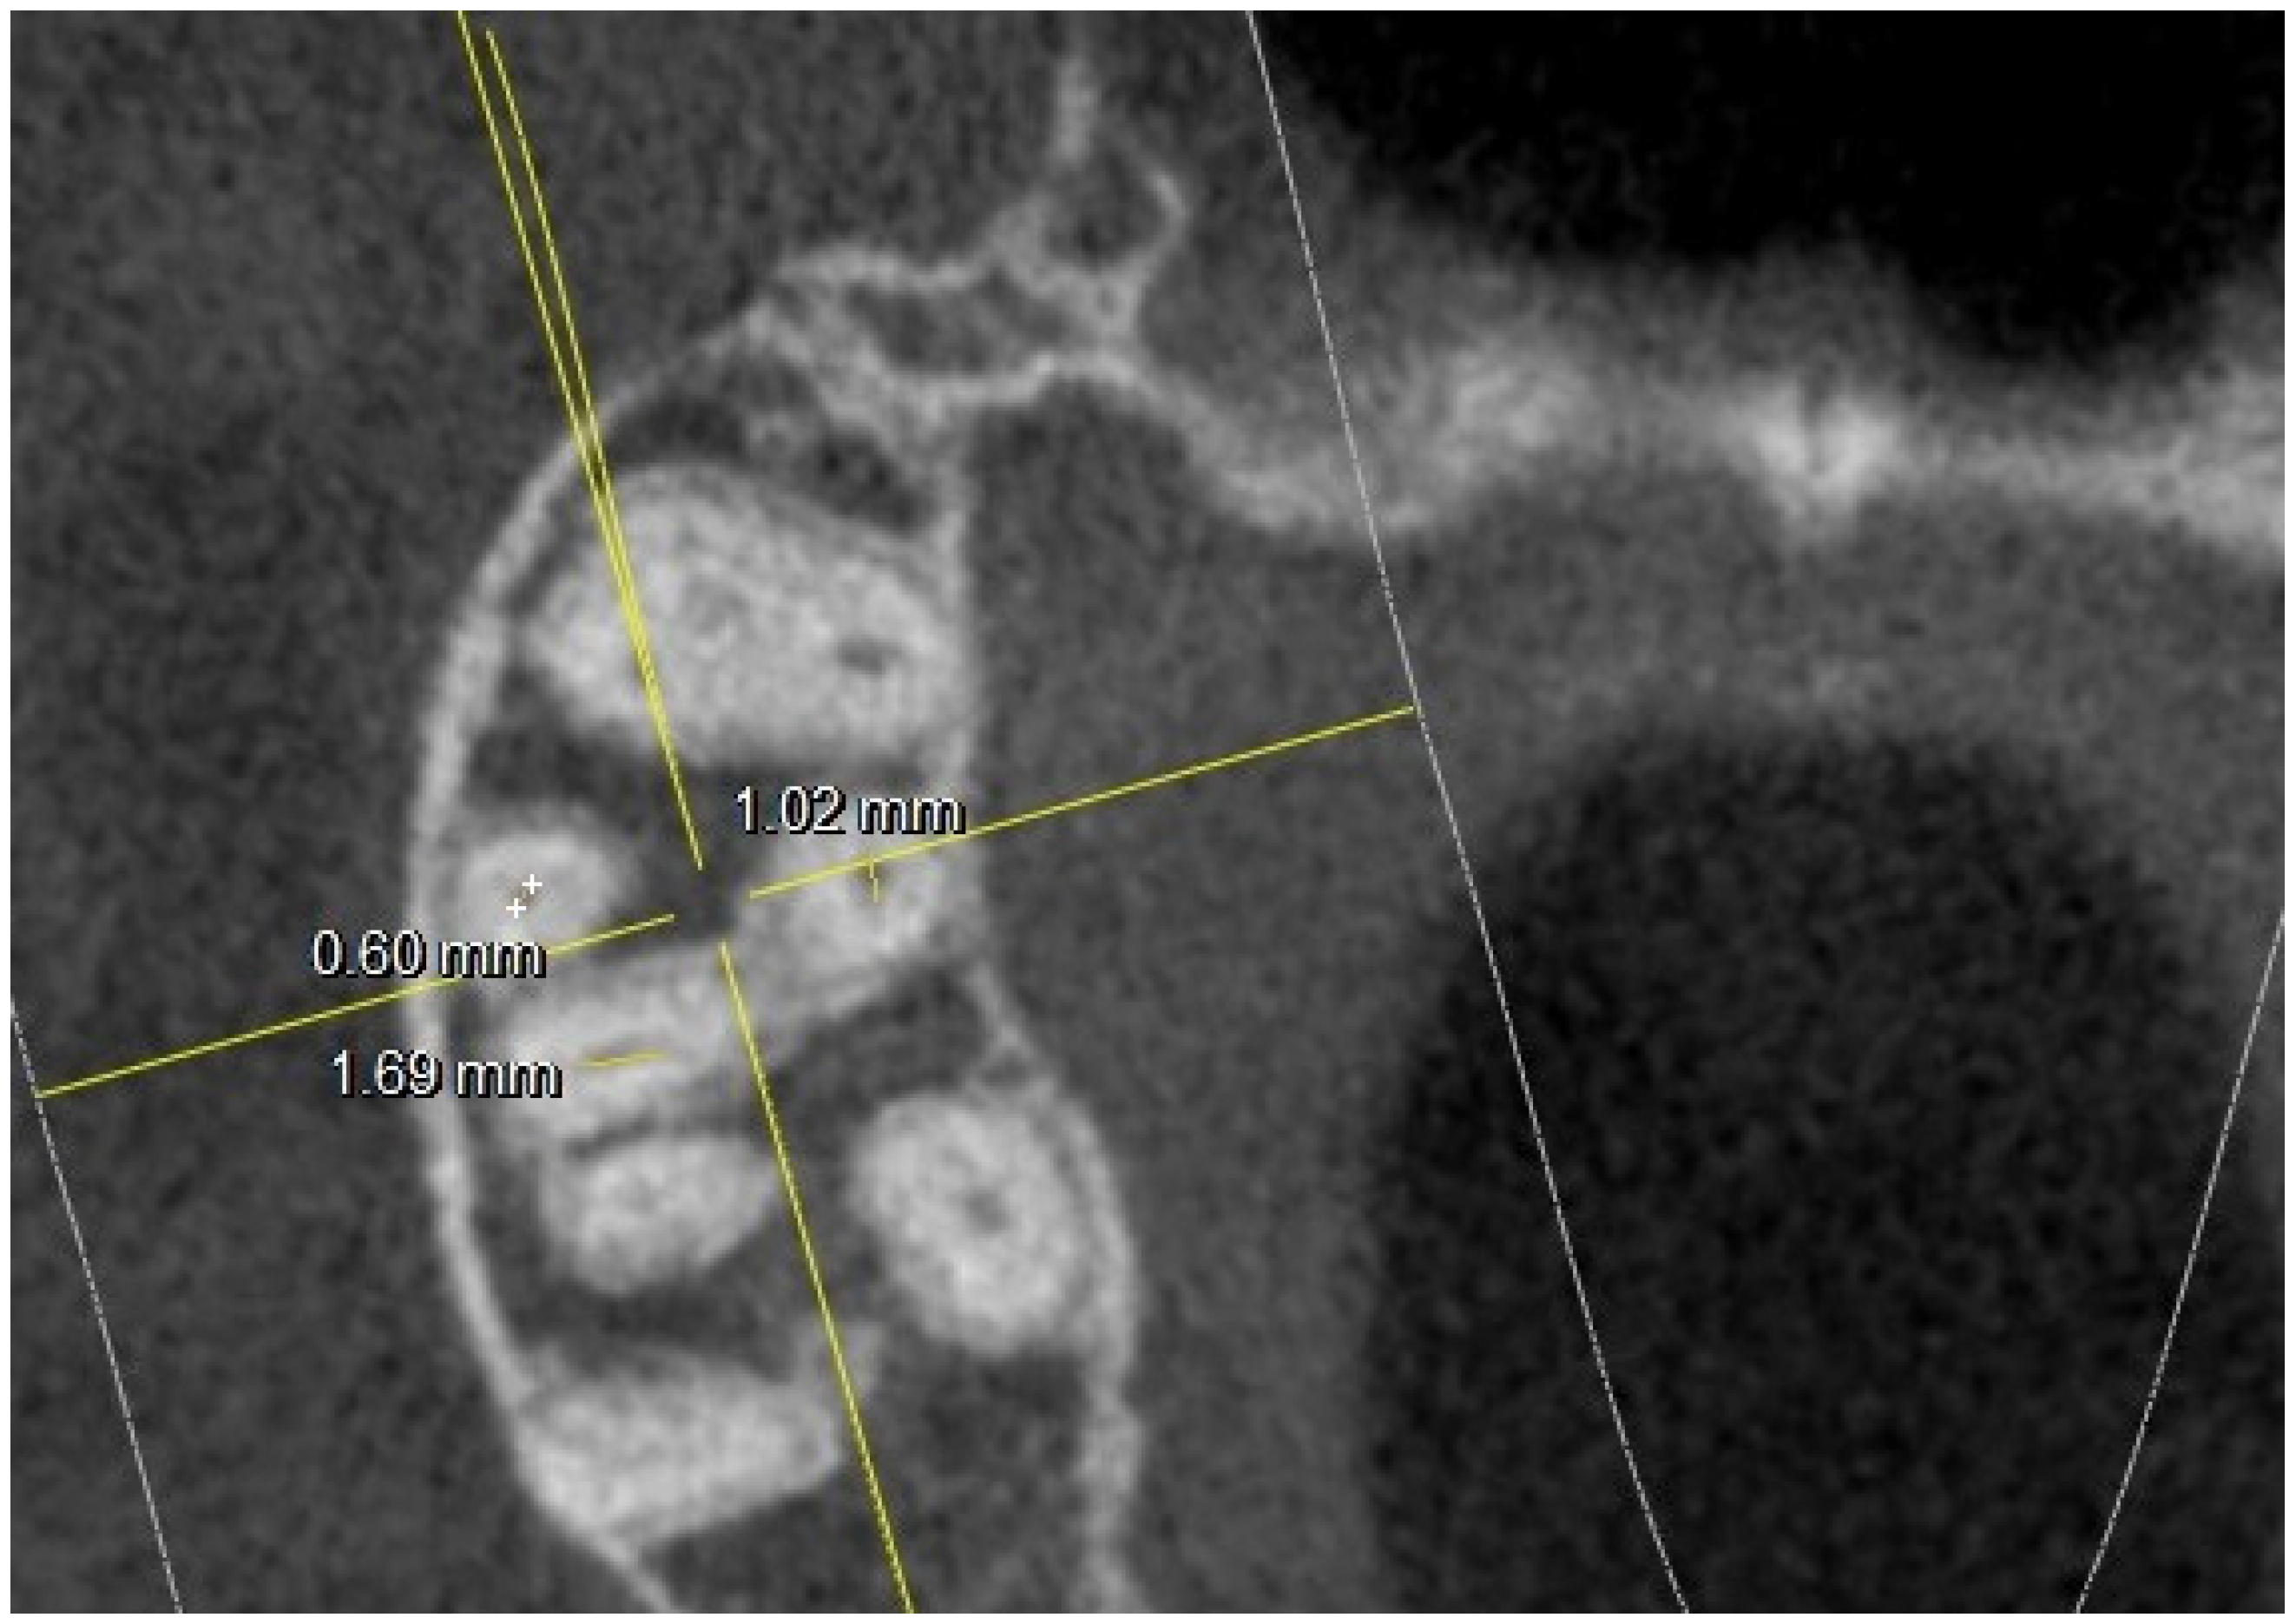

- long and short diameter of the pulp chamber floor;

- diameter of root canal orifices;

- distance between intra- and inter-root canals;

| At the orifice: M-B diameter | 0.65 | 0.21 | 0.81 | 0.17 | 0.74 | 0.24 | 0.67 | 0.21 | ||

| Mb2 diameter | 0.38 | 0.12 (6 NO) | 0.3 | 0.8 (10 NO) | 0.39 | 0.9 (3 NO) | 0.34 | 0.8 (15 NO) | ||

| At the orifice: MB-DB distance | 2.33 | 0.22 | 2.35 | 0.21 | 2.22 | 0.2 | 2.19 | 0.2 | ||

| MB1-MB2 distance | 1.54 | 0.21 | 1.67 | 0.21 | 1.63 | 0.19 | 1.45 | 0.22 | ||